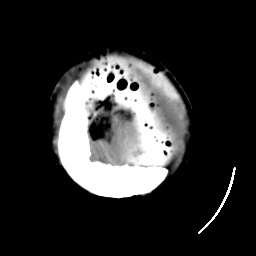

Meningioma: Roentgen-ray CT #1 -- Slice #22

[Home][Help][Clinical] Slice 22